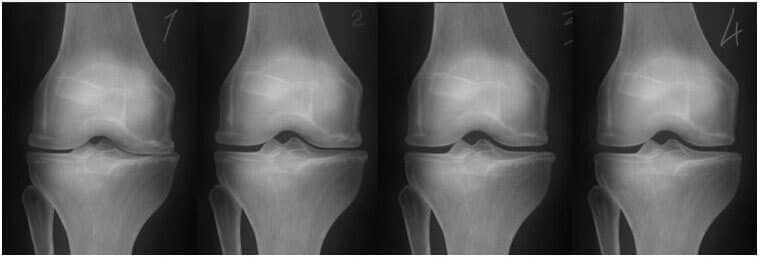

– Рендгенските снимки подолу ја покажуваат типичната слика за заздравувањето на зглобот на коленото.